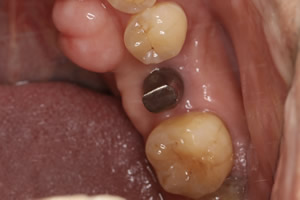

症例2

- 年齢・性別

- 57歳男性

- 治療期間

- 3ヶ月

- 抜歯

- なし

- 治療費

- 165万円

- 備考

- 左上5.6.7 及び左下6.7欠損

- 治療内容

- 左上5.6.7と左下6.7欠損部にインプラント埋入

- 施術の副作用(リスク)

- オペによる知覚障害。インプラントによる歯肉炎。インプラント脱落。